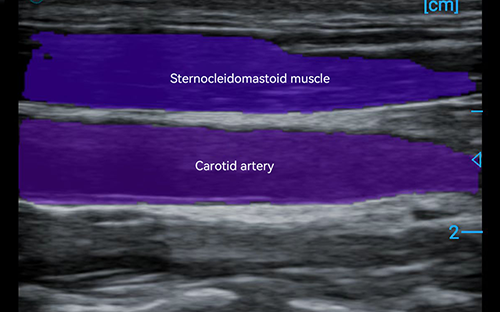

PIU1A features an advanced linear probe with high frequency and resolution that captures detailed images of superficial tissues, MSK systems, and vessels. It’s vital across scenarios: aiding pain management by visualizing soft tissue issues, supporting emergency FAST exams, and diagnosing sports injuries, such as muscle strains, for targeted treatment. Its clarity ensures clinicians to make more confident and accurate decisions.

PIU1A sets a new standard for image clarity in portable point-of-care MSK diagnostics, ensuring every detail of targeted tissues is rendered with remarkable precision—right at your fingertips. This exceptional image quality stems from its advanced spot reduction technology, engineered with Beamformer and Plane Wave Compounding algorithms that deliver consistent, high-fidelity imaging.